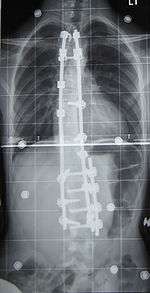

Preoperative (left) and postoperative (right) X-ray of a person with thoracic dextroscoliosis and lumbar levoscoliosis: The X-ray is usually projected such that the right side of the subject is on the right side of the image; i.e., the subject is viewed from the rear (see left image; the right image is seen from the front). This projection is typically used by spine surgeons, as it is how surgeons see their patients when they are on the operating table (in the prone position). This is the opposite of conventional chest X-ray, where the image is projected as if looking at the patient from the front. The surgery was a fusion with instrumentation.